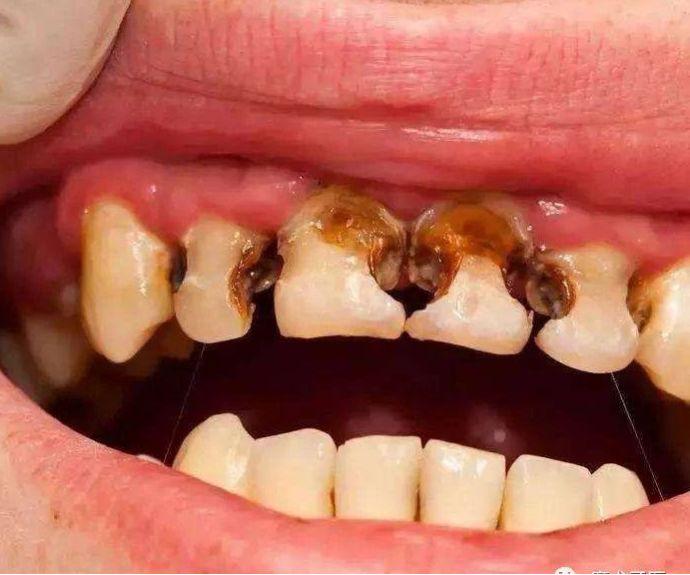

新的一年,新的變化。家長(zhǎng)們,你們有沒有發(fā)現(xiàn)自己的孩子也有了新的變化:個(gè)子長(zhǎng)高了,性格更加不羈了,牙齒也爛得差不多了(齲齒)。

中國(guó)兒童的齲齒狀況總體令人擔(dān)憂,哪怕不是留守兒童,如果身邊的父母疏于孩子的口腔健康教育,放任其養(yǎng)成愛吃糖常喝可樂(lè)刷牙不自覺等等壞習(xí)慣,終牙齒的境況也基本上類似。

而且有這樣的一種現(xiàn)實(shí),哪怕全口牙齲壞也鮮有家長(zhǎng)為此主動(dòng)去看牙醫(yī),更多的是當(dāng)孩子出現(xiàn)了劇烈牙痛或者牙齦上長(zhǎng)出了令家長(zhǎng)們驚恐的如圖示腫物(恐癌心理)才被迫就診,這是一種中國(guó)式特色——反正乳牙都是要換掉的,單純齲齒治不治無(wú)所謂。

齲齒,俗稱蛀牙,蟲牙,但與蟲子完全搭不上邊,一定要搭的話,那蟲子就是細(xì)菌——變形鏈球菌為主。它作為一種產(chǎn)酸菌,只有在含糖和碳水化合物豐富的基質(zhì)上進(jìn)行化合作用才會(huì)酸蝕牙齒,而甜食,牛奶,碳酸飲料等等為它提供了充足條件。牙齒從酸蝕到脫礦崩解需要一定的時(shí)間,上面所見的嚴(yán)重齲齒病例,本來(lái)有相當(dāng)長(zhǎng)的時(shí)間去進(jìn)行早期干預(yù),無(wú)論是醫(yī)學(xué)干預(yù)還是行為改變,都能不同程度地影響疾病進(jìn)展,不致形成“豁耙齒”的境地。